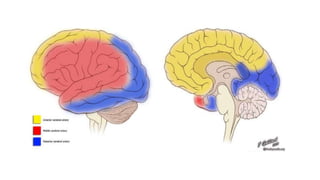

Anatomy

• -Brain represents 2% body

mass

• -Requires 15-20% total cardiac

output to function

• - Blood supply through the

internal carotid artery &

vertebrobasilar artery